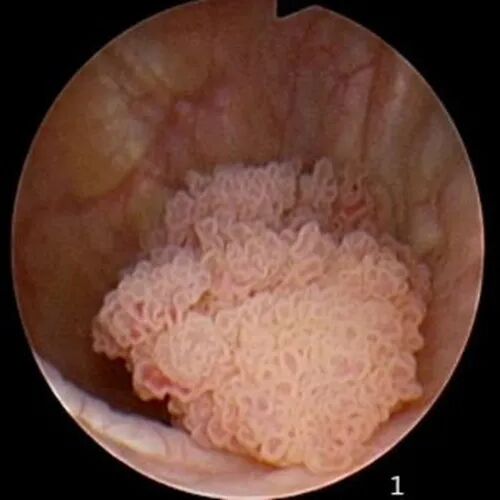

膀胱肿瘤

膀胱镜下检查可发现膀胱肿瘤,利于肿瘤的综合治疗。